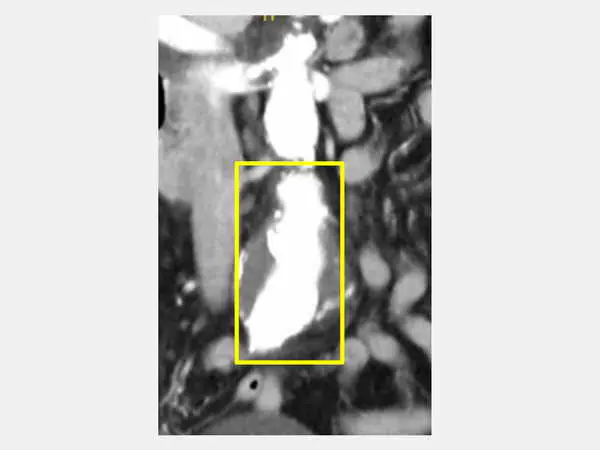

圖二:經檢查顯示腹部主動脈腫大(方框處),為腹部主動脈瘤。

心臟血管外科顏旭霆醫師說,腹部主動脈瘤是指腹部的主動脈因為血管壁變弱而擴張變形,形成「瘤樣膨脹」。當腹部主動脈瘤直徑持續變大,會有破裂風險,可能造成嚴重內出血而危及生命,高齡(常見於65歲以上)、高血壓、抽菸、家族史,以及動脈粥狀硬化者是高危險族群。